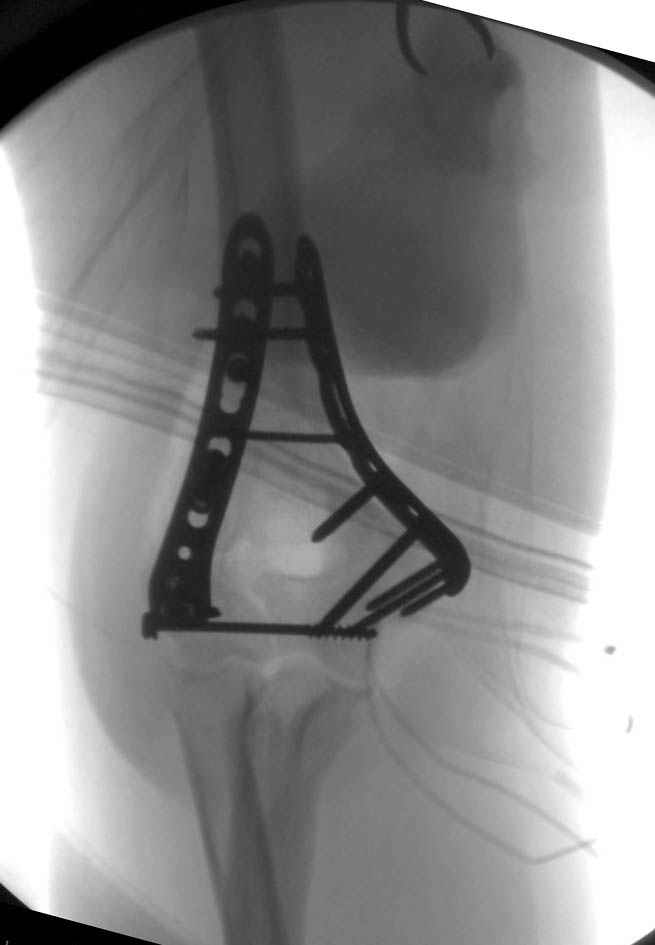

Примерный случай, только перелом был открытый, в задне-медиальной стороне рана около 2 см по характеру "изнутри кнаружи", неврологический статус со слабостью сгибания мизинца, также слабая абдукция и аддукция указательного пальца и сгибания в кисти.

Больному сделали обработку и наложили временный аппарат внешной фиксации плечо-предплечье.

На шестой день сделали открытую репозицию чрезлоктевым доступом двумя locking plate, локтевой нерв был ушибленным, после операции положительная динамика в Flexor Carpi Ulnaris. Фиксацию локтевого отростка произвели tension band technique с дополнительным шурупом.

Этапы операции на снимках....